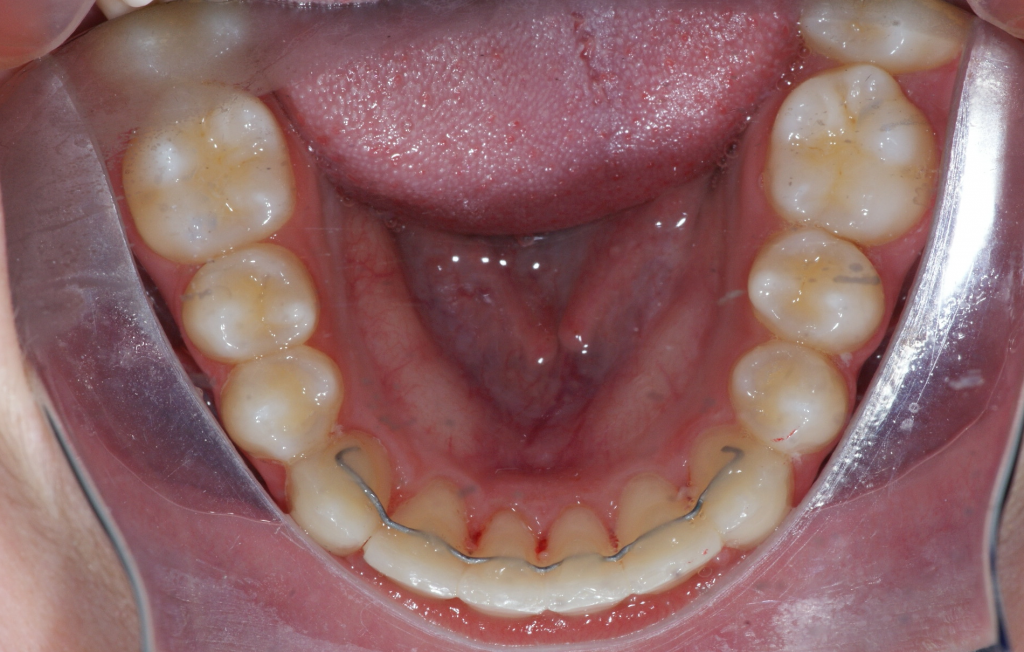

Dans la majorité des cas, un traitement complet est requis afin de corriger la malocclusion et procéder à la traction des canines incluses. Le temps de traitement varie en fonction de l’âge du patient, de la position des canines incluses et de la sévérité de la malocclusion. Ici, nous avons dû procéder à la traction de la canine incluse inférieure droite (#43). La durée du traitement fut de 19 mois, ce qui est exceptionnel puisque habituellement, on parle plus de 24 à 30 mois de traitement pour faire la traction d’une canine.